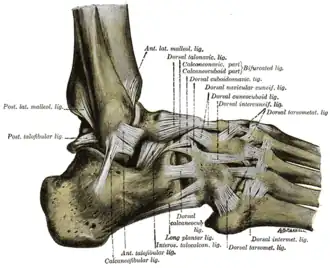

The ligaments of the foot from the lateral aspect. | |